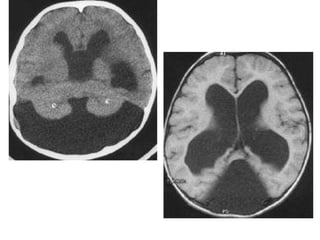

Descrição

• Hidrocefalia severa supratentorial;

• Dilatação cística do 4º ventrículo;

• Vermix pequeno;

• Afastamento dos hemisférios cerebelares;

• Ausência do teto do 4º ventrículo;

• Espessamento e opacificação da pia-aracnóide

das cisternas da base do crânio;

• Dilatação do aqueduto

Descrição • Hidrocefaliasevera supratentorial; • Dilatação cística do 4º ventrículo; • Vermix pequeno; • Afastamento dos hemisférios cerebelares; • Ausência do teto do 4º ventrículo; • Espessamento e opacificação da pia-aracnóide das cisternas da base do crânio; • Dilatação do aqueduto